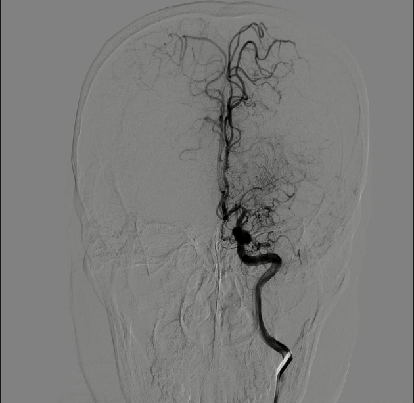

入院影像检查

MRA

DWI

重要影像结论:左侧额顶叶梗死灶(急性或亚急性期),较3月前明显增大,左侧大脑中动脉闭塞。